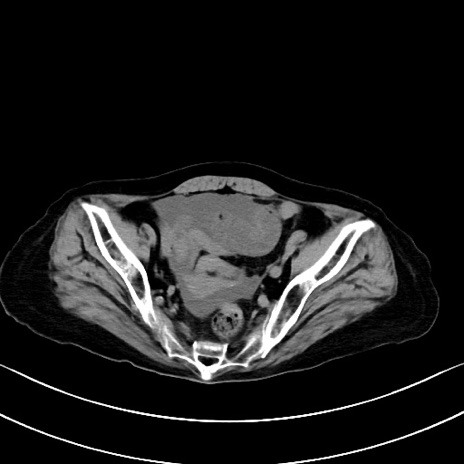

横断像

他院CT